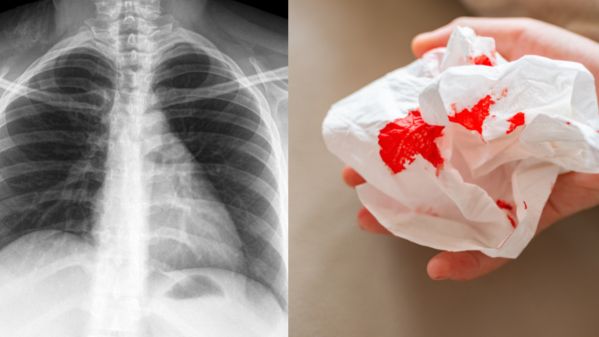

Tuberculosis is a bacterial infection caused by Mycobacterium tuberculosis. It spreads through the air when a person with active pulmonary TB coughs, sneezes, laughs or even talks.

Here are the key tuberculosis symptoms to watch for:

If you’re searching for “persistent cough more than 2 weeks Malaysia”, don’t ignore it. Early TB screening can prevent complications and stop the spread to family members.